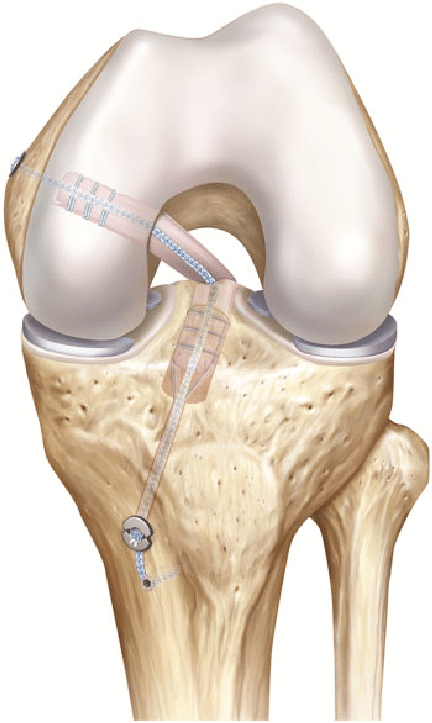

Reconstrucția ligamentului: LIP rupt este, de obicei, reconstruit, nu suturat. Se utilizează un grefon, de obicei prelevat din altă parte a corpului pacientului(autogrefa) sau de la un donator (alogrefa). Integrarea completă a grefonului în os durează câteva luni.

Intervenția chirurgicală se efectuează, de regulă, artroscopic (cu incizii mici), ceea ce implică o recuperare mai rapidă și dureri postoperatorii mai reduse.